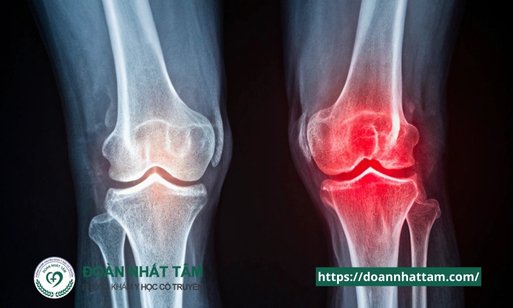

Đau khớp gối là một trong những vấn đề sức khỏe phổ biến nhất, ảnh hưởng đến hàng triệu người trên toàn thế giới. Từ

Cứng khớp gối là tình trạng phổ biến gây khó chịu và ảnh hưởng đến vận động. Bài viết này sẽ giúp bạn nhận diện

Đau Khớp Gối: Nguyên Nhân, Triệu Chứng và Cách Điều Trị Hiệu Quả” “Đau khớp gối là tình trạng phổ biến, ảnh hưởng đến chất